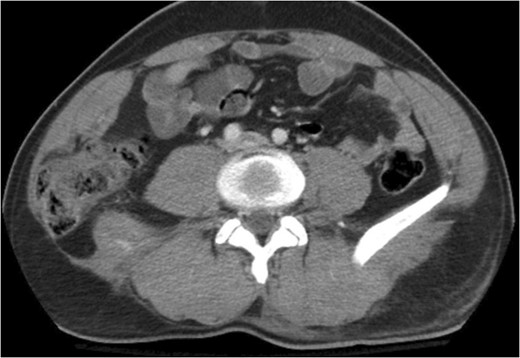

A 43-year-old male patient presented with a right-sided traumatic lumbar hernia after a blunt mechanism. The patient had been pinned between a dirt-mover’s claw arm resulting in a crush mechanism. He sustained injuries to the lumbar spine, sacrum, abdominal wall and 12th rib. On presentation, he did not have clinical or radiographic evidence necessitating abdominal exploration and was observed in a monitored setting. Computed tomography imaging demonstrated a Grynfeltt defect with herniation of the ascending colon and cecum through an area defined by the 12th rib, quadratus lumborum and internal oblique (Figures 1 and 2). After several days of observation and recuperation, the patient continued to have significant pain overlying the hernia site. We electively brought him to the operating room on post-injury Day 4. A laparoscopic repair of the traumatic hernia was performed. Key operative steps included: (i) Wide exposure of the hernia defect via incision of the peritoneum and transversalis as well as mobilization of the ascending colon and duodenal sweep (Figures 3 and 4). (ii) Primary repair of the defect with intra-corporeal suturing of the oblique musculature (Figures 5 and 6). (iii) Placement of an underlay mesh with appropriate redundancy at least 4 cm in all directions around the defect and seating against the iliac crest (Figure 7). Post-operative imaging demonstrates obliteration of the hernia defect and restoration of the abdominal wall (Figures 8 and 9). The patient has recovered, returned to the work force and has no pain or bulge at the repair site 6 months after injury.

Step 1 begins with incision of the peritoneum overlying the hernia.